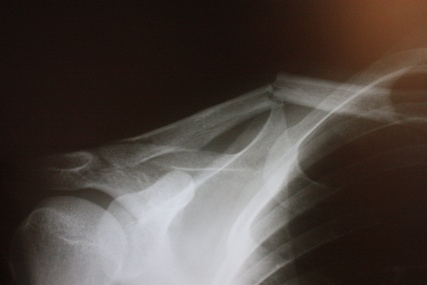

보드 타다가 넘어져서 좌측 쇄골이 부러졋네요,,,'

외국이라 한국나갈때까지 기다리고 잇습니다,,똑부러졋고요...팔들기가 어려운데,,,움직이면 어깨에 욱씬 하는 통증이 잇네요,,,원래 그런건가요...

아주 제대로 똑 부러졌군요...다행입니다.

저렇게 똑부로진 상태로 붙겟죠?? 일자 쇄골은 무린가 ㅜㅜ 부러져서 인지 왼쪽어깨가 처지고 좁아졋네요,,,ㅜㅜ 헬스를 즐기고 몸 만드는걸 조아해서 맘이 아프다는,.ㅜㅜ 정말 님 말씀대로 하루하루가 지옥이네요,,,ㅎㅎㅎ

일반적으로,똑 부러졌으면 뼛조각들이 없습니다.

산산히 뼛조각들이 있다면 수술은 절대로 잡해 집니다.그나마 다행인 겁니다.

단순 골절이라 자연 치유 가능성 100%입니다.

다만 8주간의 안정가료가 필요하며, 처음 4주간은 붙었다 떨어졌다하면서 지내실겁니다.